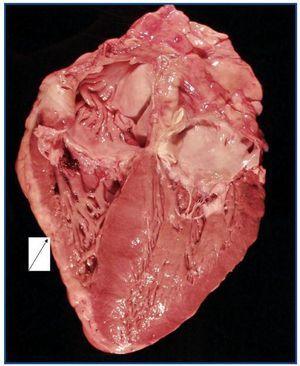

La necropsia demostró un proceso fibrosante sistémico (Figuras 1-4), con afectación de pelvis menor, retroperitoneo, en coraza alrededor de riñones, glándulas suprarrenales y páncreas, abarcando espacio periesplénico y perihepático; y mediastínico, en coraza alrededor de pericardio, arco aórtico y grandes vasos; y paquipleuritis derecha con fibrosis calcificada. Se apreciaron también: pancreatitis crónica fibrosa asociada, atrofia testicular, fenómenos de enfermedad aterombólica, hipertrofia ventricular izdª, y hepatopatía fibrosa crónica, en el contexto de un paciente con arteriosclerosis generalizada severa, con repercusión renal -nefroangiosclerosis bilateral con atrofia renal derecha, encefálica –infarto antiguo quístico izquierdo a nivel de ínsula-, y de colon –colitis isquémica rectosigmoide.

Se ha descrito también que la mayoría de pacientes que fallecen por FSN lo hacen por complicaciones cardiovasculares19, tal y como ocurrió en nuestro paciente. Los enfermos con mayor mortalidad son aquellos que tienen una severa enfermedad previa9, incluso son enfermos con menor afectación cutánea y mayor cardiovascular19. La dosis acumulada de gadodiamida importante, más una dosis elevada de eritropoyetina más un producto calcio-fósforo elevado, sería igual a un mayor riesgo para contraer la FSN, es decir, la existencia de la enfermedad previa severa, constatada por la presencia de un estado inflamatorio activo2,16.

En las autopsias se han encontrado cantidades apreciables de gadolinio, hierro y aluminio en corazón, vasos sanguíneos y piel de estos enfermos19.

Figura 4.